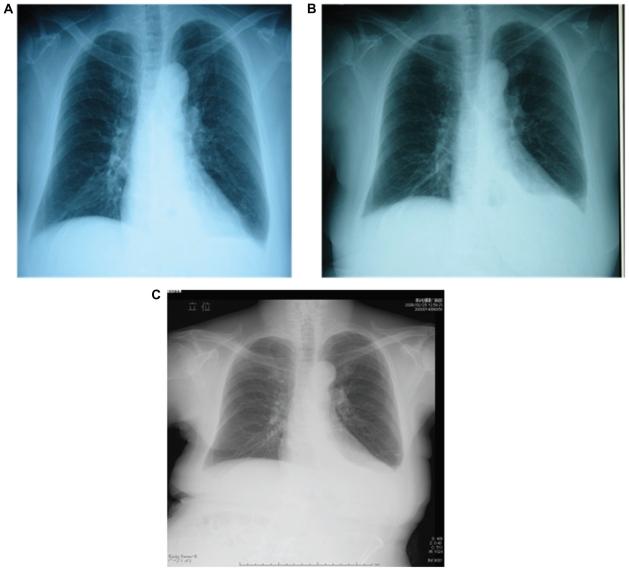

We report a case of a 67-year-old woman with rheumatoid arthritis with yellow nail syndrome (YNS) that was caused by bucillamine. All three signs (yellow fingernails, lymphatic edema, and bronchiectasis) of YNS manifested, with characteristic timing, first with the nails turning yellow after when bronchiectasis was noticed. We reviewed 10 case reports from Japan and compared the periods until the appearance of yellow nails after starting bucillamine treatment, as well as those until lung disease and leg edema appeared.